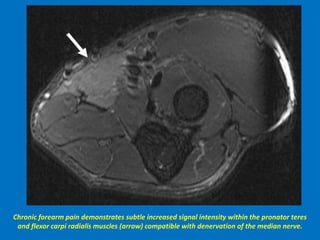

Chronic forearm pain demonstrates subtle increased signal intensity within the pronator teres

and flexor carpi radialis muscles (arrow) compatible with denervation of the median nerve.